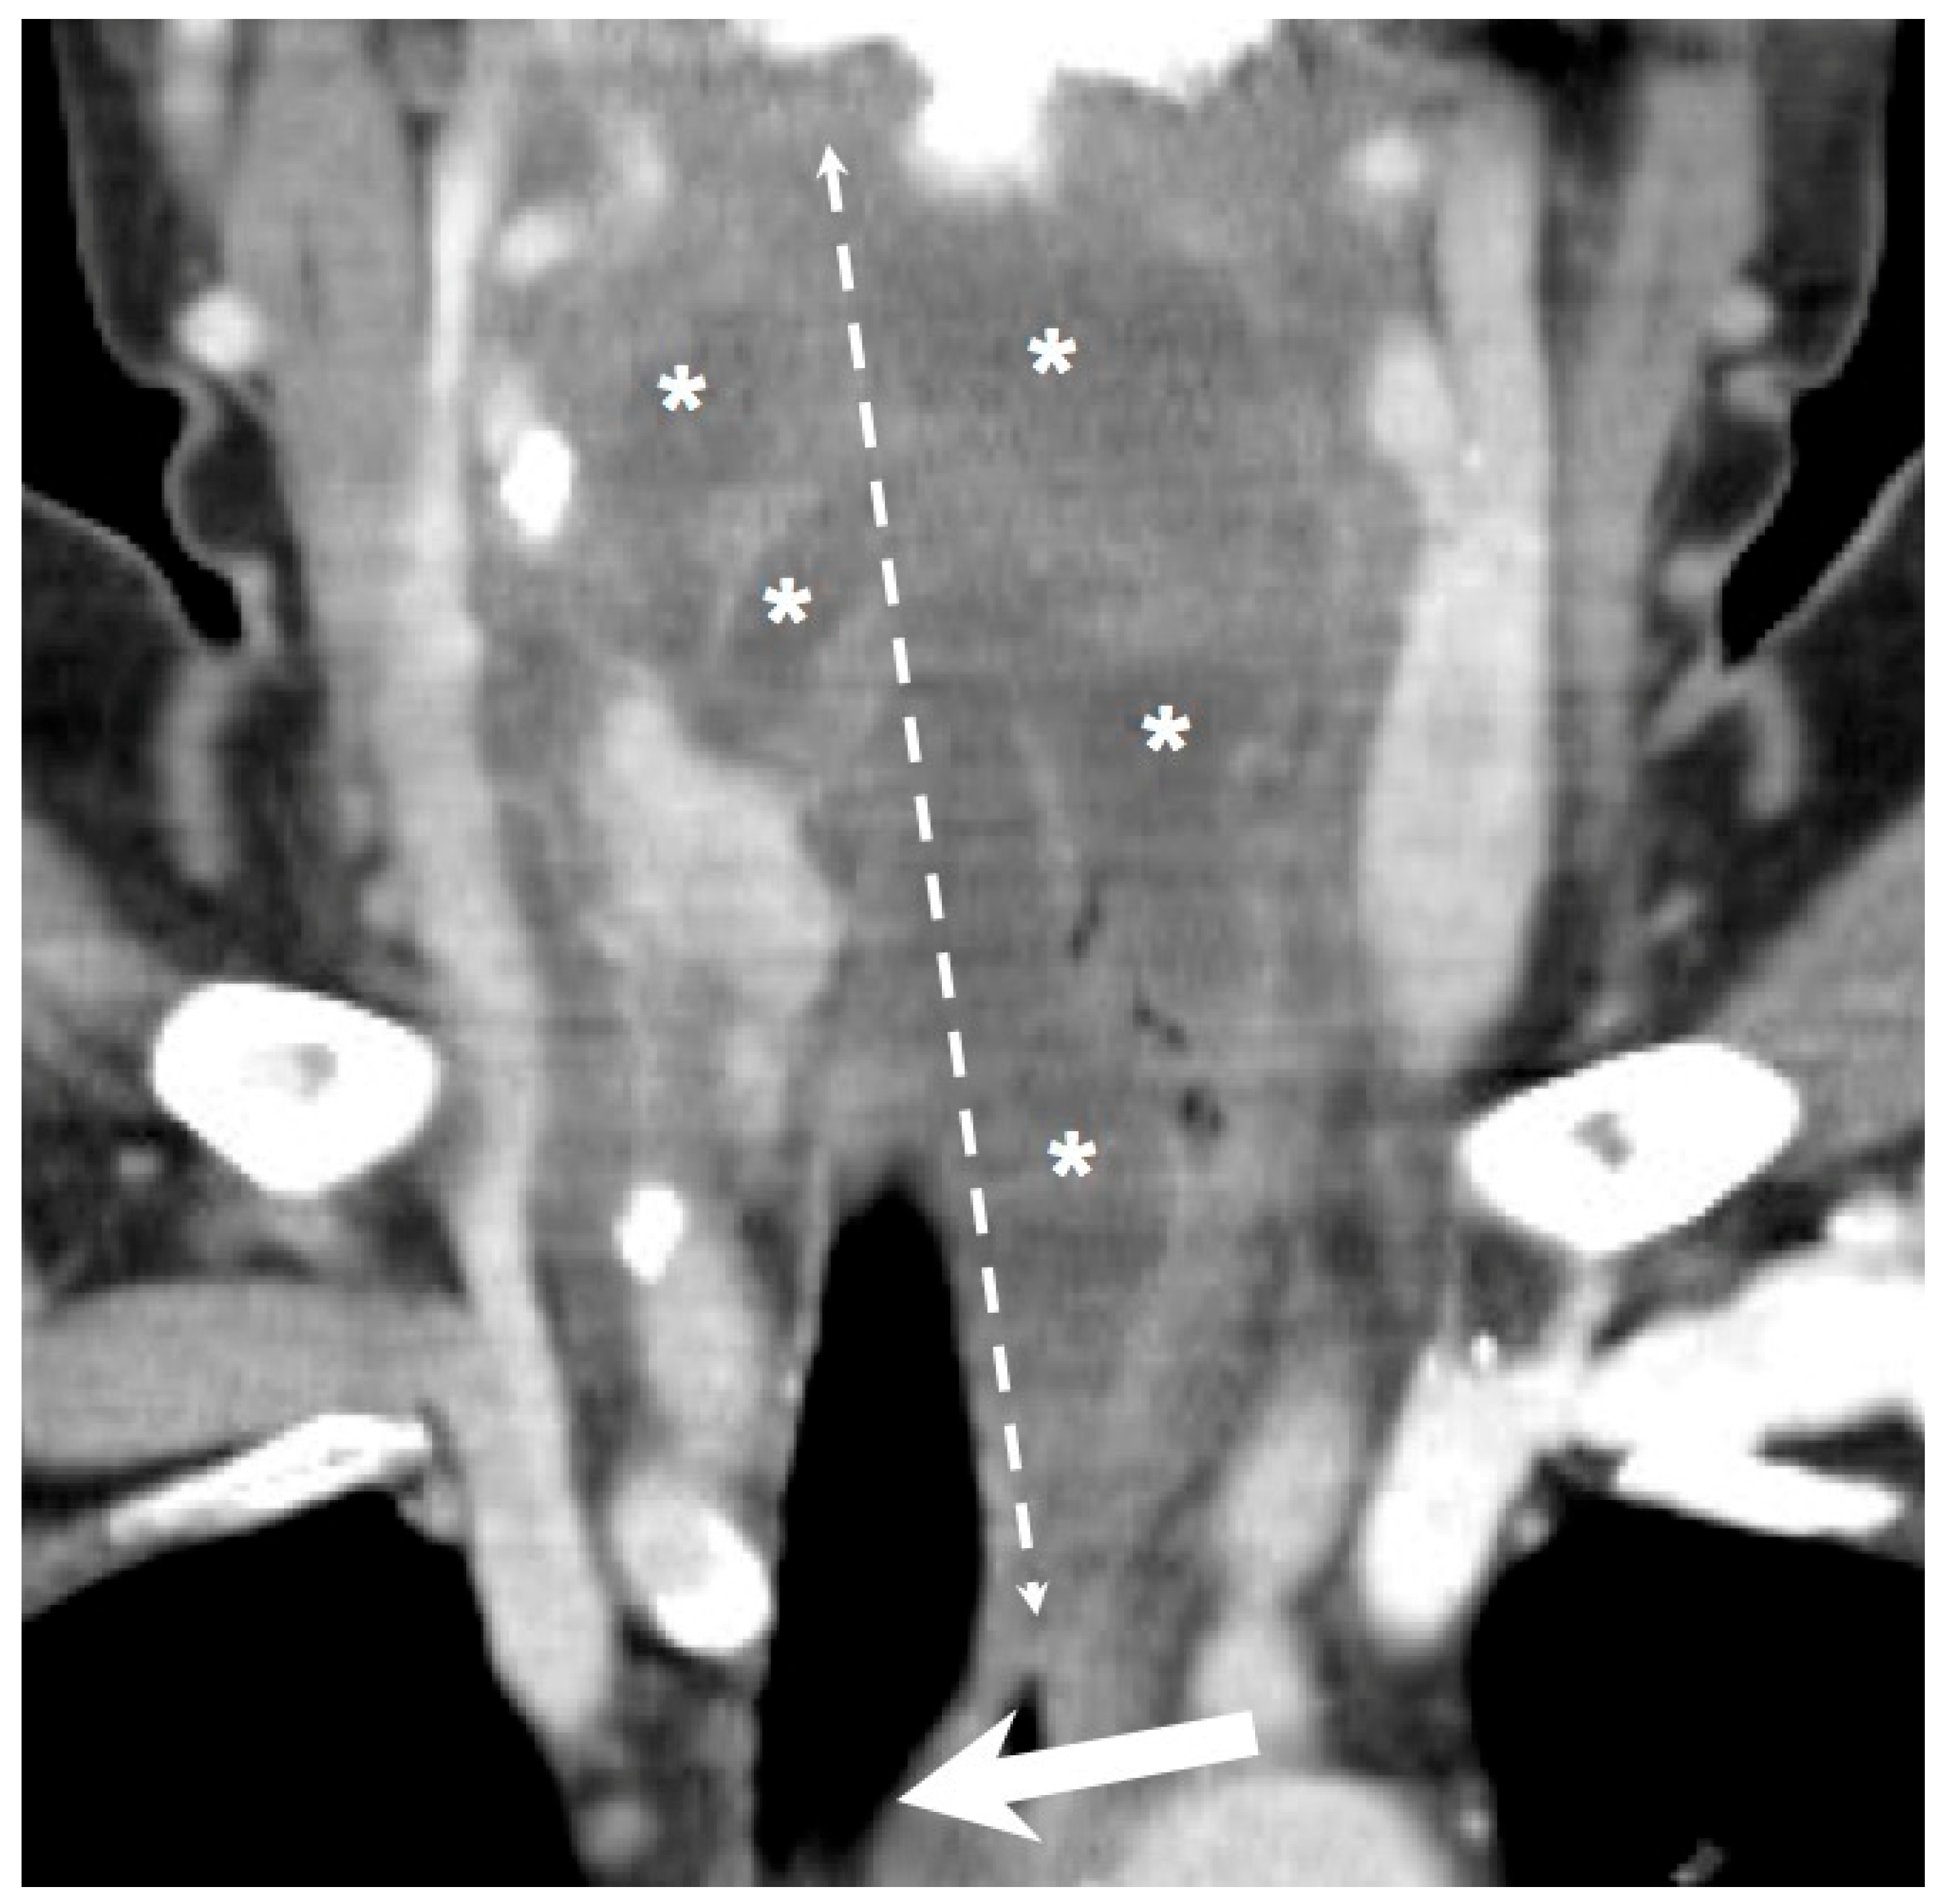

Figure 2.

The coronal view showed extensive infection in the retropharyngeal spaces with poor DM control. Arrow: compromised and deviated airway; Asterisk; multiloculated deep neck abscess; Double dotted arrow: involved spaces of DNI. (300 × 300 dpi).